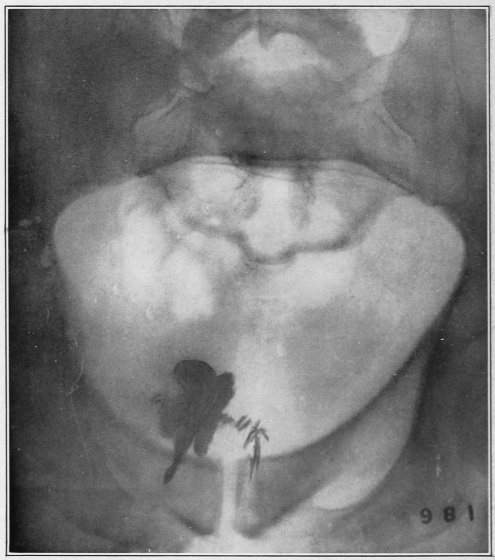

Fig. 6.

9. The anus. Levator ani muscle seen on each side. 8, 8. The rectum. 7. Beginning of the rectum. 6. The sigmoid flexure. 5. The descending colon. 4. The transverse colon. 3. The cæcum, or caput coli. 2. Appendicula vermiformis. 1. The end of the ileum.